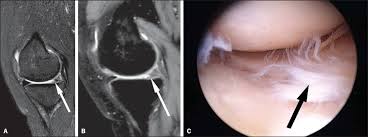

Leave time for filling out paper work and getting dressed for the scan as well. The knee mri can take 30 minutes to an hour. Slices must be sufficient to cover the whole lower leg anterior to posterior. In other cases, it might take a few days. Most knee mri scans take about 30 minutes,. Meet scott, a technologist for michigan residence imaging. Diagnostic radiology 42 years experience. The images can be stored on a computer or printed on film. A patient with knee pain may undergo an mri to enable a doctor to make a diagnosis. How long does it take to get mri results? In some situations, you may get your mri scan results back in as little as a few hours. Specifically for a knee mri, you will likely go in feet first and can generally expect the lower half of your body to be inside of the tube. The test most often lasts 30 to 60 minutes, but may take longer.

Expect to hold still for around 15 to 45 minutes, sometimes longer, while the machine makes images of your. An appropriate angle must be given in the axial plane (parallel to the right and left shaft of tibia). A doctor is trained for over 11 years (many specialists are trained even longer) to make the right decisions on behalf of patients. Does involuntary knee spams interfere with the scan? We scan axial (top to bottom) sagittal (right to left) and coronal (front to back).

Leave time for filling out paper work and getting dressed for the scan as well. During your mri, you'll hear loud noises like thumping and tapping as the machine goes to work. 1  it works by creating a magnetic field that causes the water molecules in tissue, bones, and organs to orient themselves in different ways. How long does an mri of the knee take to do? There are no known harmful effects from the strong magnetic field used for an mri. Mri results can take days or weeks depending on how comprehensive the scans were. The test most often lasts 30 to 60 minutes, but may take longer. We scan axial (top to bottom) sagittal (right to left) and coronal (front to back). Diagnostic radiology 42 years experience. These orientations are then translated into images we can use for diagnosis. Meet scott, a technologist for michigan residence imaging. In other cases, it might take a few days. But the magnet is very powerful.